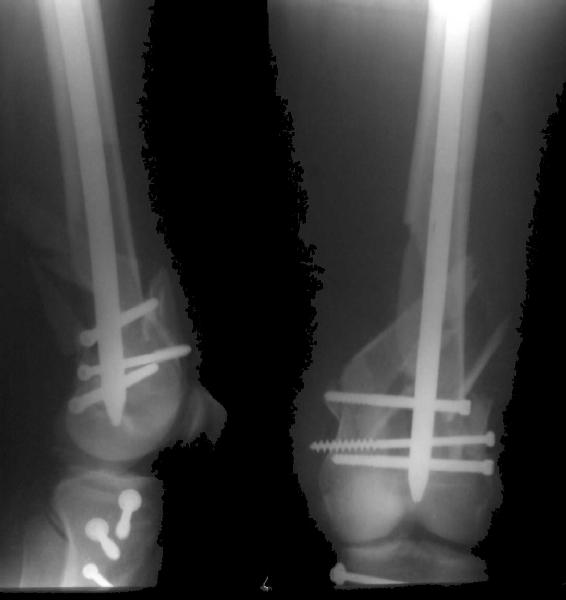

THX, initial images are

1,

2.

KEMMD> - Your last posted case: how is possible to have secure fixation with

KEMMD> applied construct without additional casting, bracing or Ilizarov?

At that moment we had in stock only the 10 mm solid nails so of course there was no idea about early weight bearing. But it was quite enough for early knee ROM excersises (see attached). Two locking screws through the distal block provided that.

A new toy is more interesting and fashionable. And anyway it is not panacea, i have already seen presentations with LISS failures like the attached one presented by D.Seligson. And people also demonstrated incisions say that the method is not so LESS invasive as it supposed to be.